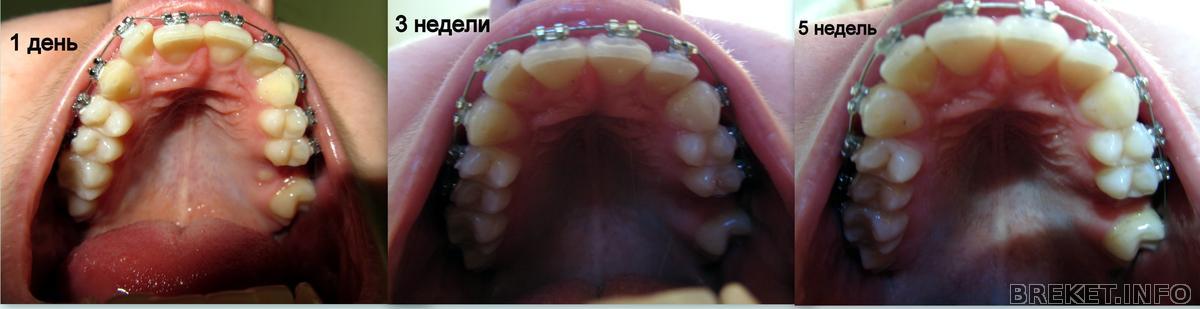

Всем привет. Первый день рождения в брекетах. Результаты ошеломляющие,а прошло всего-то 5 недель. 30 июня иду ставить на низ. Зубы до сих пор болят если ими кусать,а в остальном будто и нету брекетов. Фото прилагается :

kollazh_1d-3-5_nedel.jpg